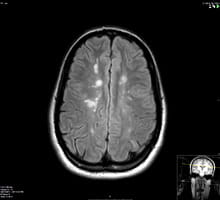

Multiple Sclerosis

Multiple sclerosis or MS is an immune-mediated disorder in which the patients’ own immune system attacks their brain and/or their spinal cord causing inflammation and scarring. It commonly manifests in the form of relapses and remissions but some forms of the disease are progressive. It can cause variable neurological manifestations and it usually affects young adults. Early and prompt treatment can prevent relapses and slow down or prevent disability. Learn more about multiple sclerosis.